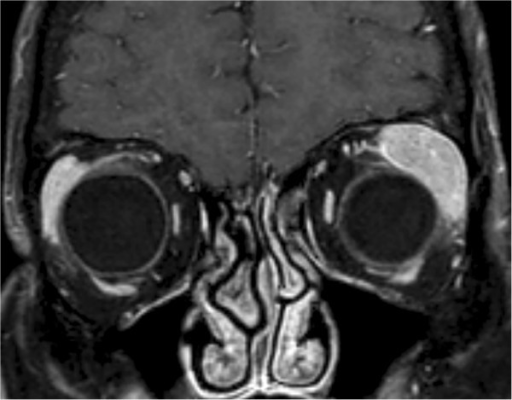

- CT/MRI: molding 양상 (주변 구조물을 따라 퍼지며, 골 침범 없음)

안와 림프종의 CT 특징: molding pattern — 종양이 주변 구조물을 파괴하지 않고 사이사이로 퍼지는 양상. 해면혈관종(well-defined round mass)과 감별됩니다.